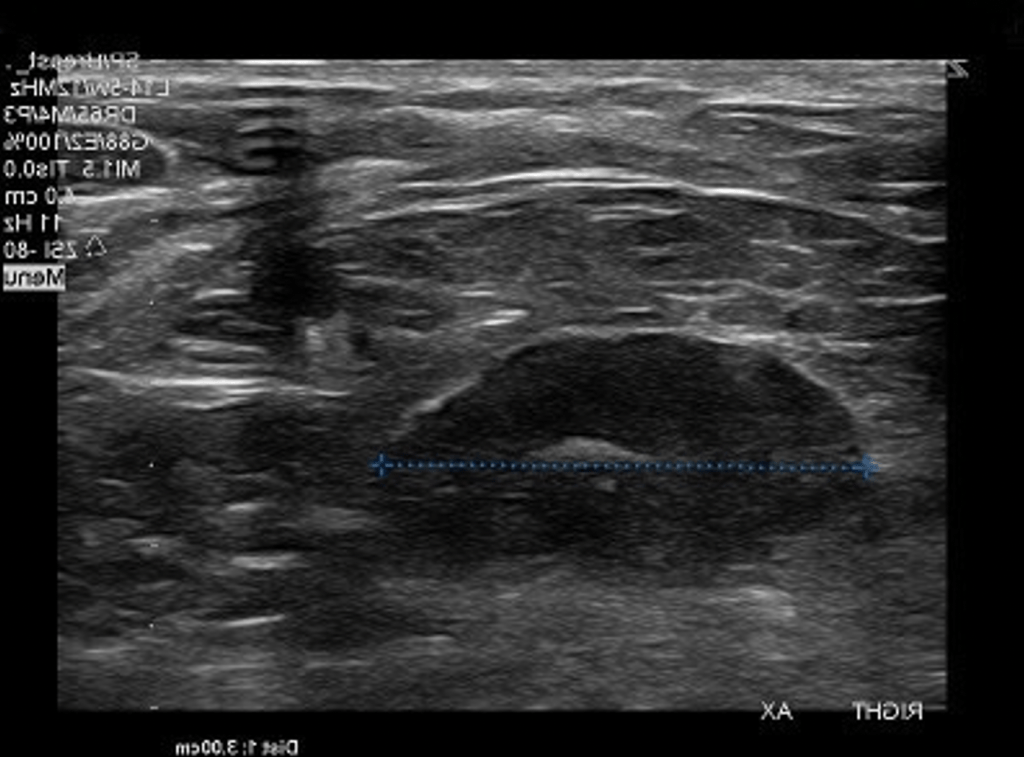

- Breast ultrasound:

- Typically seen as a well-circumscribed, round to ovoid, or macro-lobulated mass with generally uniform hypoechogenicity

- Intralesional sonographically detectable calcification:

- May be seen in approximately 10% of cases

- Sometimes a thin echogenic rim (pseudo capsule) may be seen sonographically

- On ultrasonograms:

- Fibroadenomas appear as:

- Circumscribed, homogeneous, oval, hypoechoic masses:

- That may have gentle lobulations

- A smooth, thin, echogenic capsule

- Variable acoustic enhancement; and homogeneity